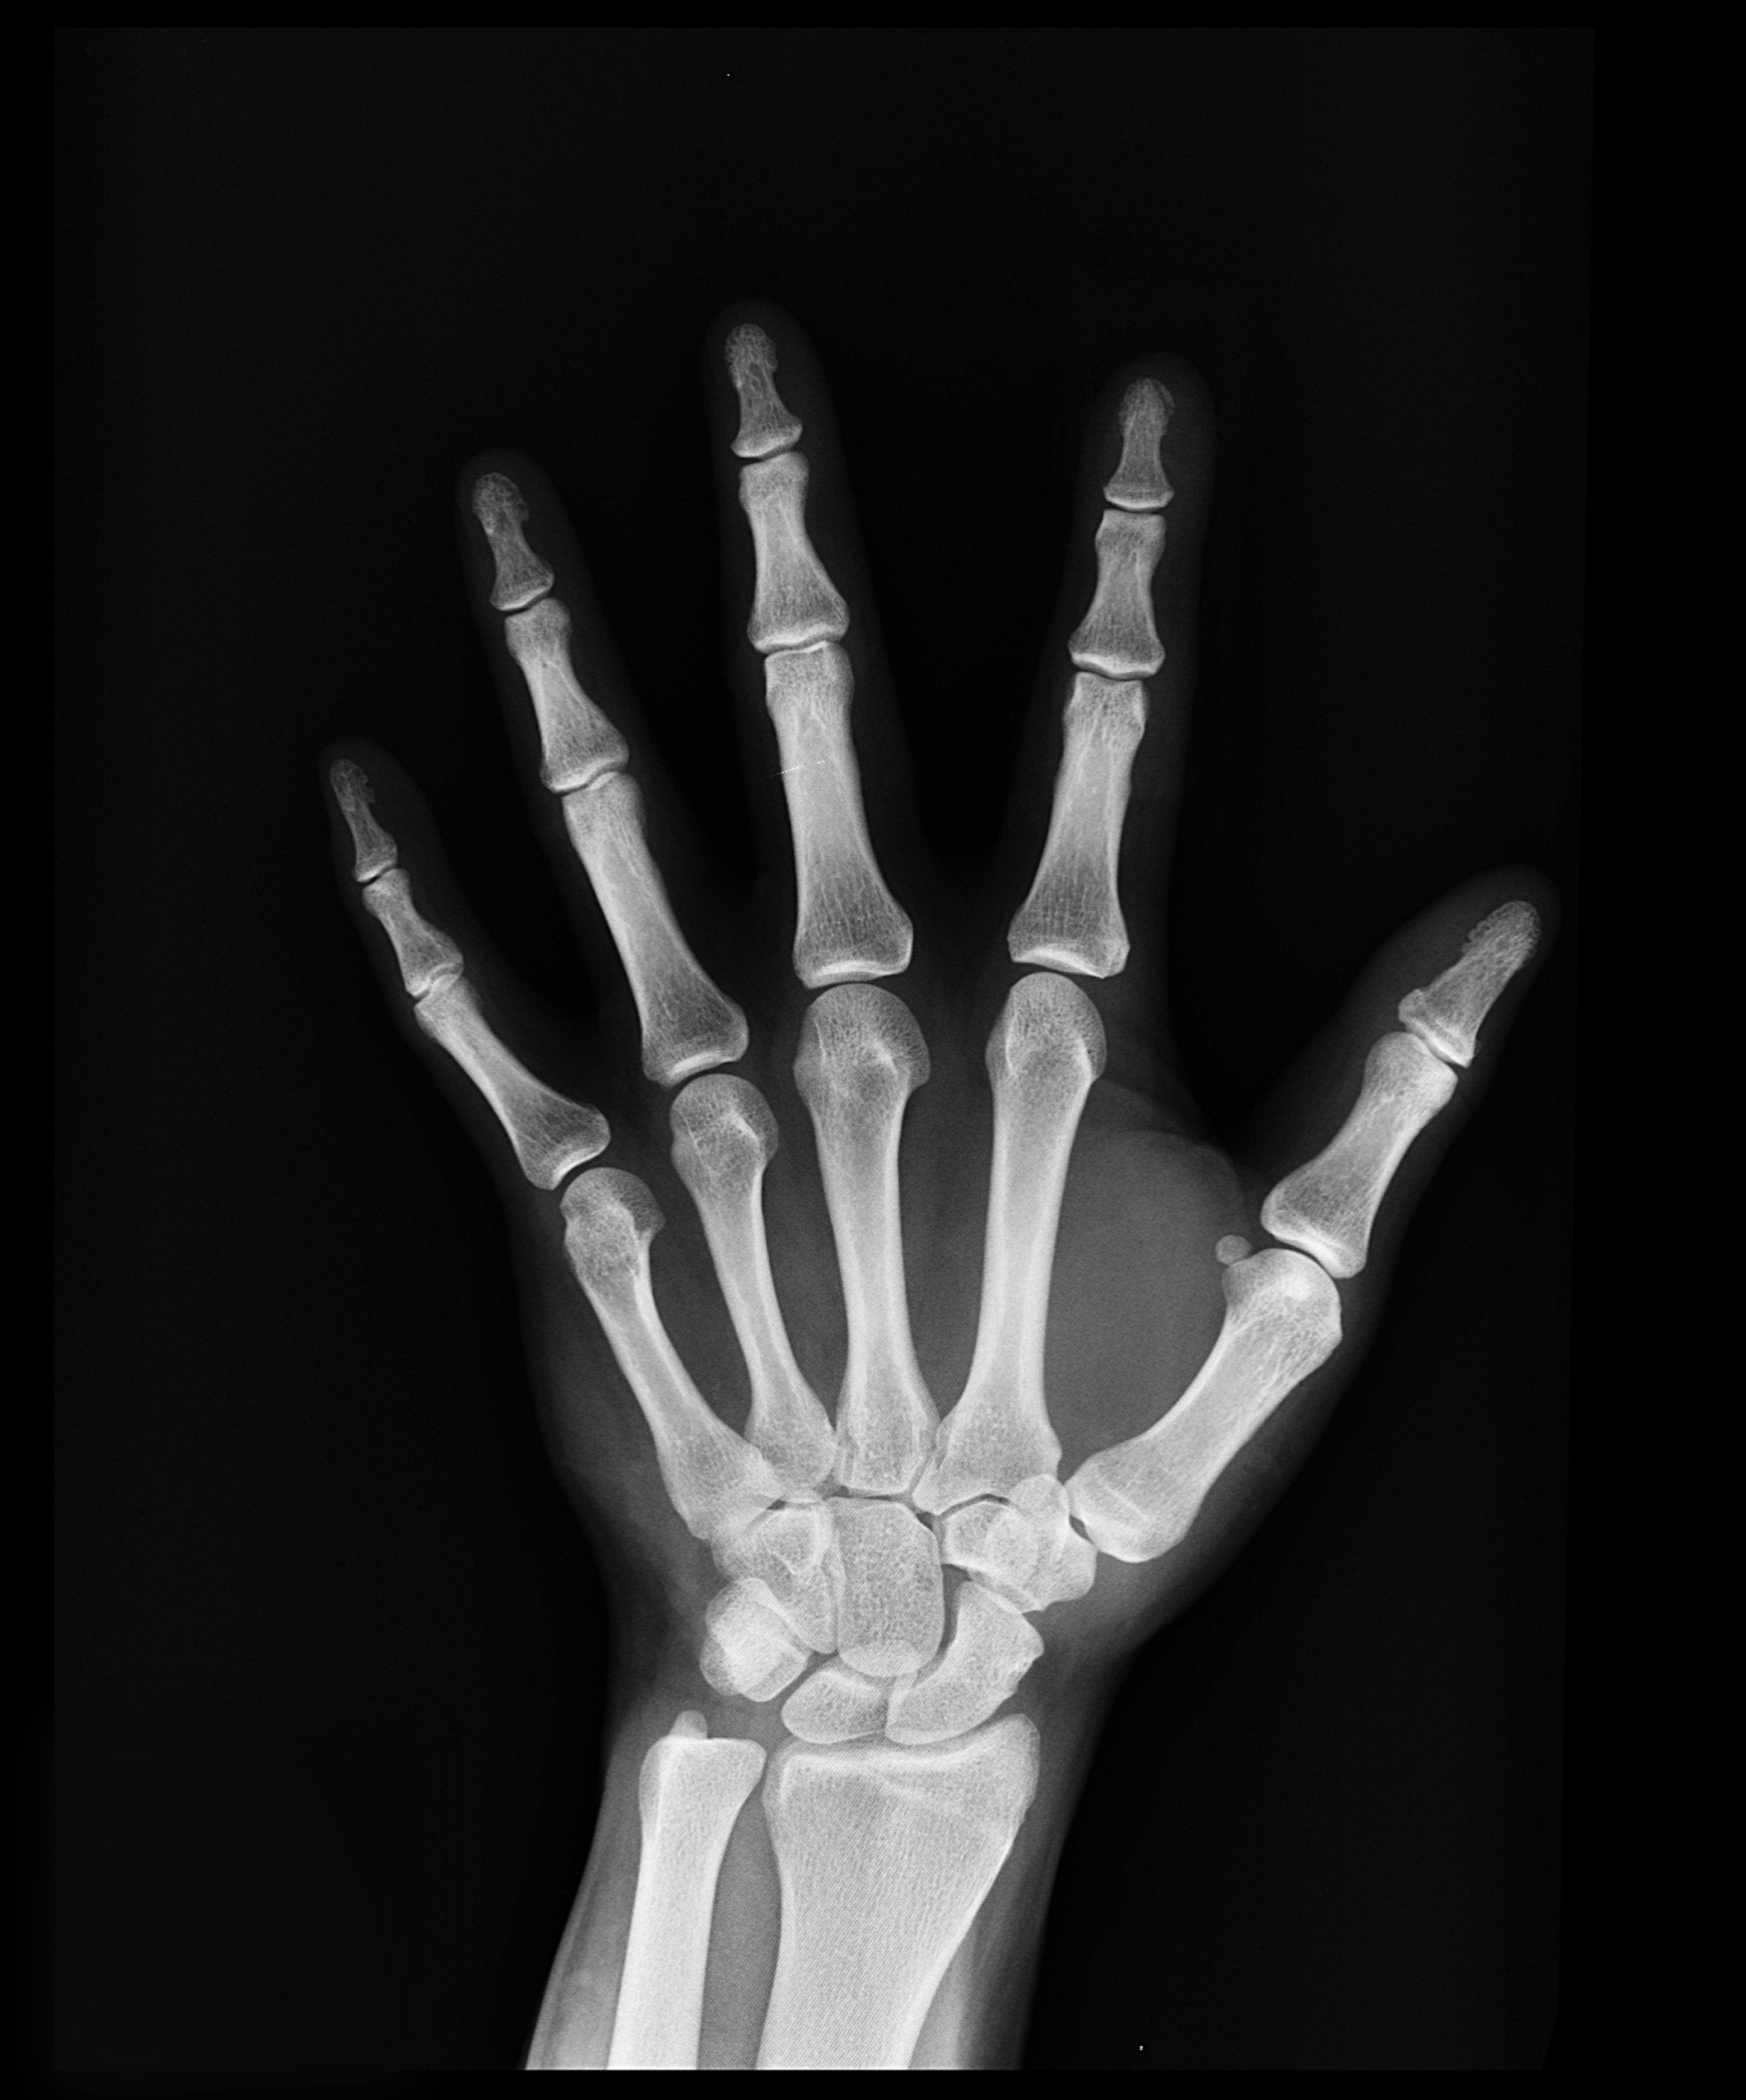

손가락 퇴행성 관절염은 나이가 들면서 관절을 보호하는 연골이 점점 닳아 없어지며 발생하는 만성 질환이다. 손가락 관절은 우리가 일상생활에서 가장 많이 사용하는 부위 중 하나이기 때문에, 관절염이 발생하면 통증과 뻣뻣함으로 인해 손을 자유롭게 움직이기 어려워진다. 특히 손가락을 많이 쓰는 직업을 가진 사람이나 반복적인 손 사용이 많은 사람에게 발생할 확률이 높으며, 여성에게 더 흔하게 나타난다. 초기에는 가벼운 불편함으로 시작되지만, 점차 관절이 변형되고 기능이 저하될 수 있어 조기 관리와 예방이 중요하다.

4) 관절 변형

진행된 관절염에서는 손가락이 굽거나 옆으로 휘어지는 변형이 나타날 수 있다. 관절이 튀어나와 울퉁불퉁한 모양이 되며, 헤버든 결절(손가락 끝마디)이나 부샤르 결절(중간 마디)이 생길 수 있다.